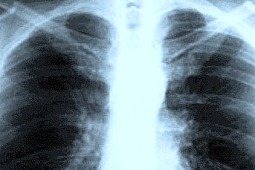

- W RTG – plamiste i zlewające się zaciemnienia, jednolite zacienienia płata oraz obecność płynu w jamie opłucnej.